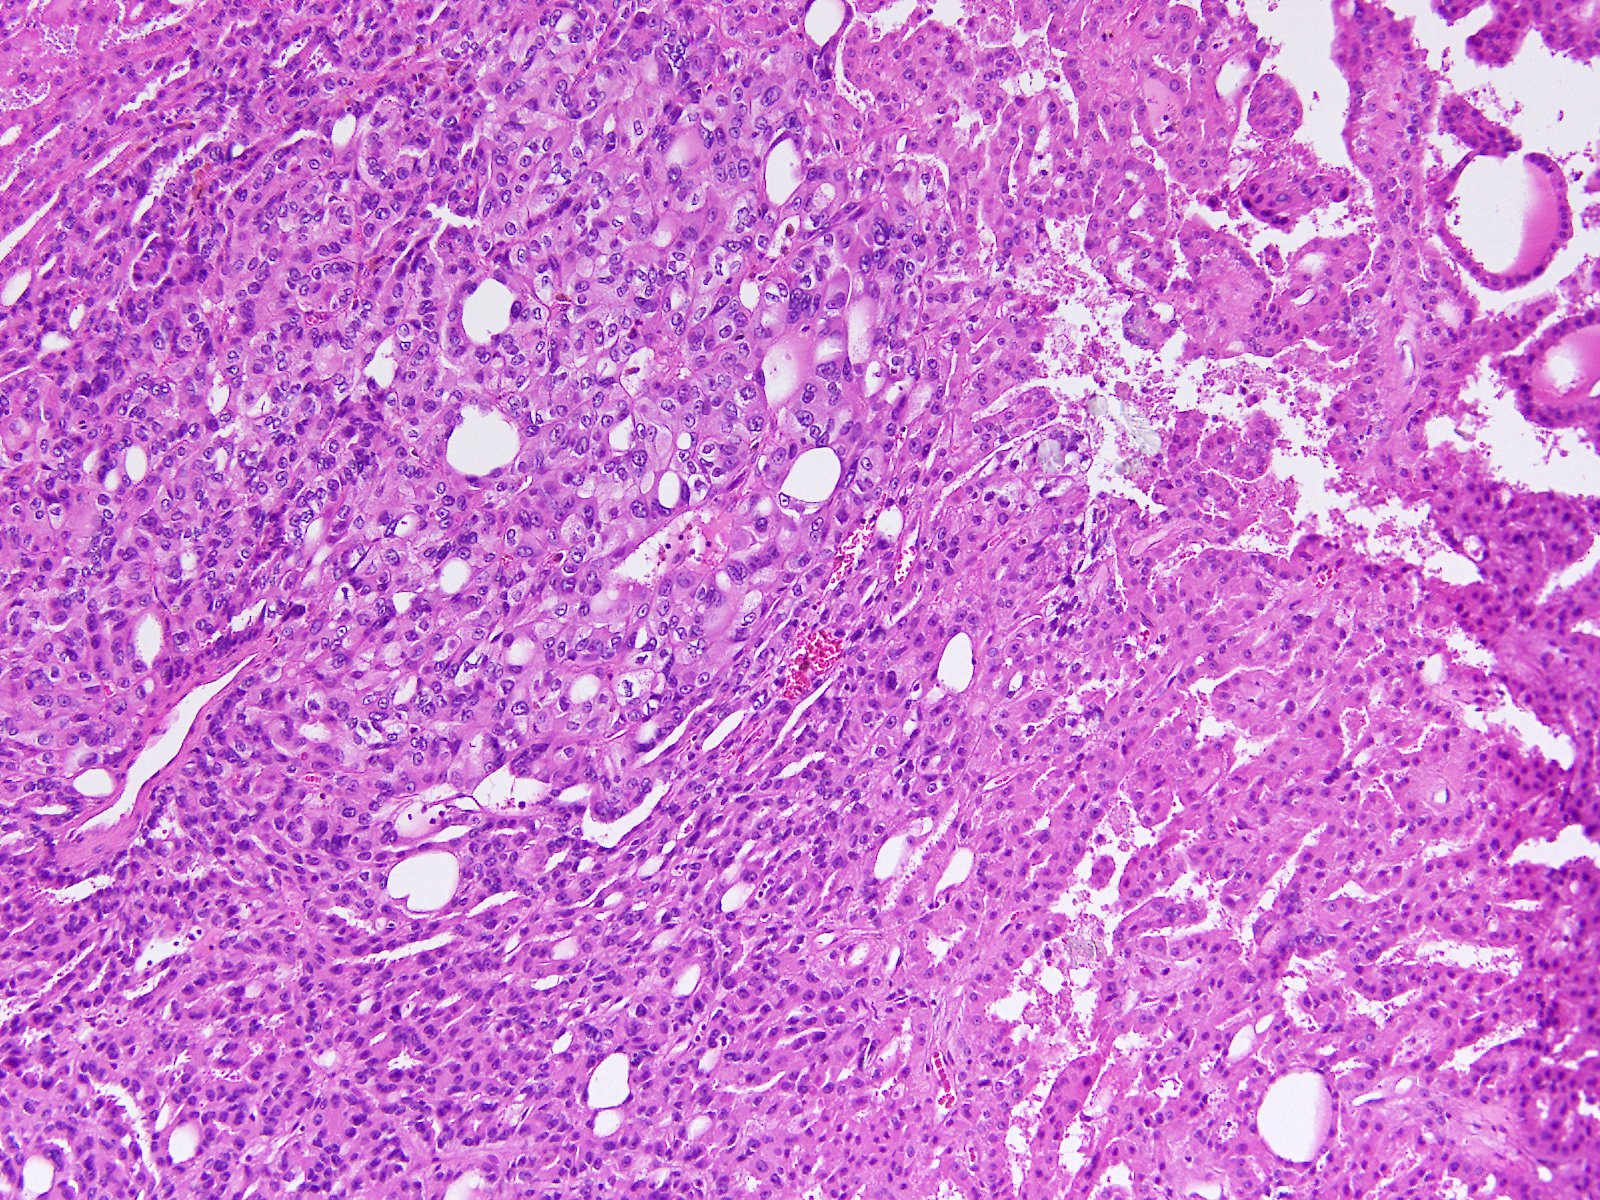

Consensus grade: Acquired cystic disease-associated RCC

User Diagnosis Difficulty Comment

Pathologist 1 Acquired cystic disease-associated RCC Typical

Pathologist 2 Acquired cystic disease-associated RCC Typical

Pathologist 3 Acquired cystic disease-associated RCC Typical

Pathologist 4 Acquired cystic disease-associated RCC Typical

Pathologist 5 Acquired cystic disease-associated RCC Not typical

Pathologist 6 Acquired cystic disease-associated RCC Not typical

Need info of the background kidney tissue

Pathologist 7 Acquired cystic disease-associated RCC Typical

Pathologist 8 Acquired cystic disease-associated RCC Typical

Pathologist 9 Acquired cystic disease-associated RCC Typical

Pathologist 10 Acquired cystic disease-associated RCC Not typical

Pathologist 11 Acquired cystic disease-associated RCC Not typical

Pathologist 12 Acquired cystic disease-associated RCC Typical

Pathologist 13 Acquired cystic disease-associated RCC Typical

Pathologist 14 Renal cell carcinoma, unclassified Not typical

Features of papillar,y clear cell and ACD RCC.

ISUP grade 2

Pathologist 15 Renal cell carcinoma, unclassified Not typical

Pathologist 16 Acquired cystic disease-associated RCC Typical

Pathologist 17 Acquired cystic disease-associated RCC Not typical

More papillary RCC type, however crystaloids are suggestive for ACRD ass RCC. Again, like in previous case.....if there is anamnesis of ESKD....I would vote for ACRD ass RCC

Pathologist 18 Acquired cystic disease-associated RCC Typical